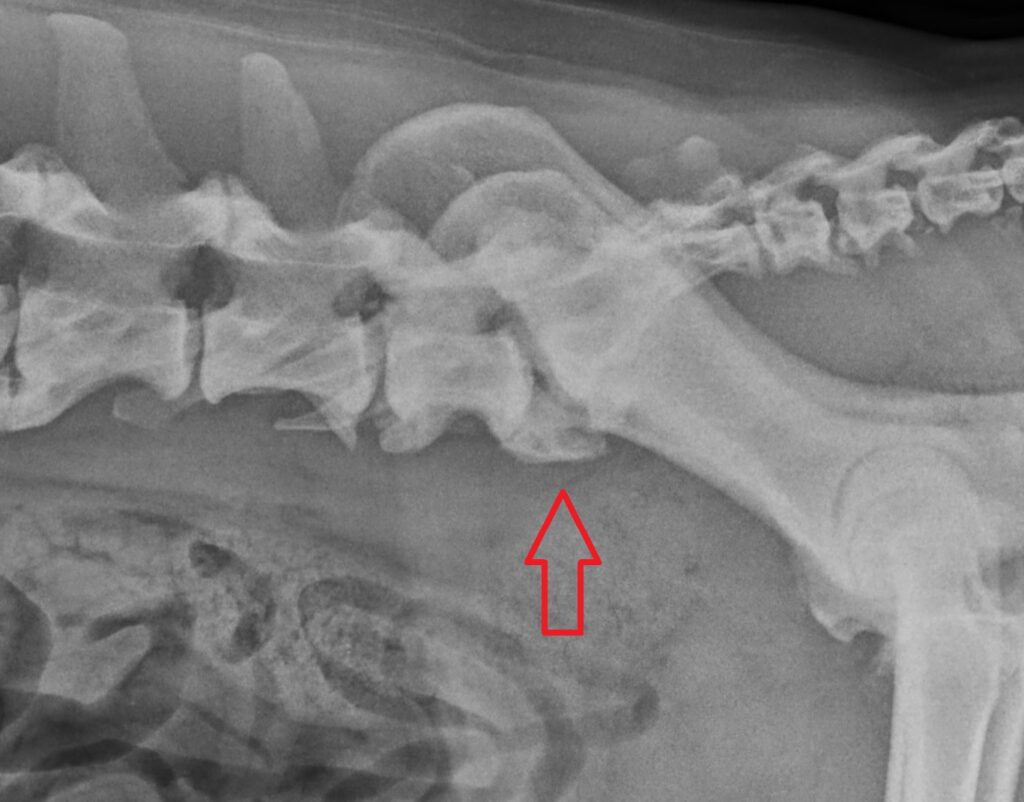

Lumbosacral Disease in Dogs

Lumbosacral Disease refers to a degenerative condition at the junction between the last lumbar vertebra (lower spine) and the sacrum (pelvis). In simple terms, it’s a problem that affects the nerves leaving the lower back, leading to pain, stiffness, and mobility issues.